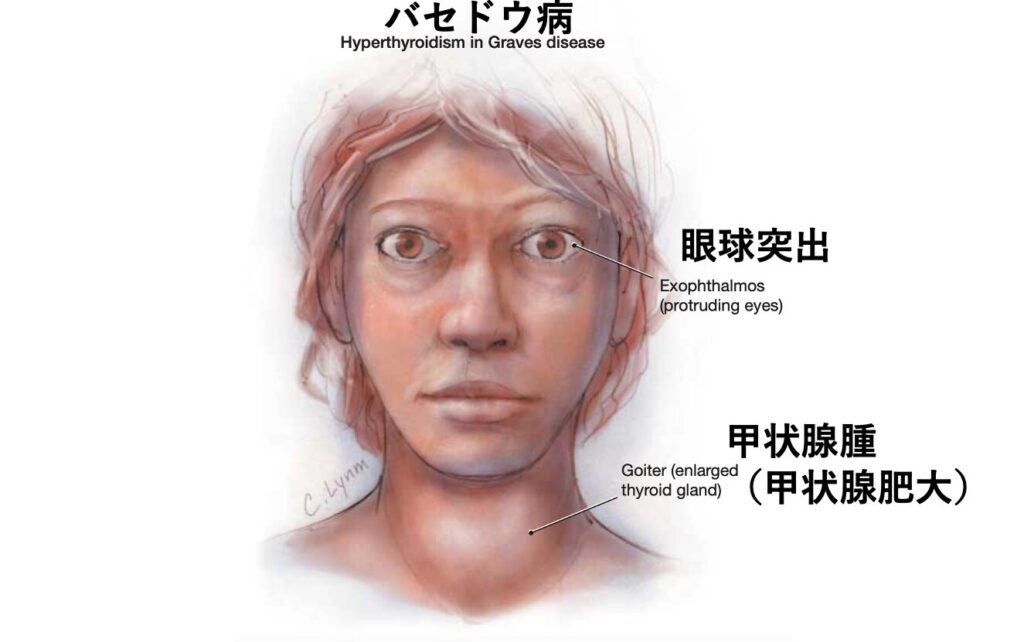

症状

バセドウはドイツのメルゼブルグで診療を行っており、バセドウ病患者の特徴として眼球突出・頻脈・甲状腺腫を報告しました。メルゼブルグで見つけた3徴であることから後にメルゼブルグの3徴と呼ばれるようになりました。